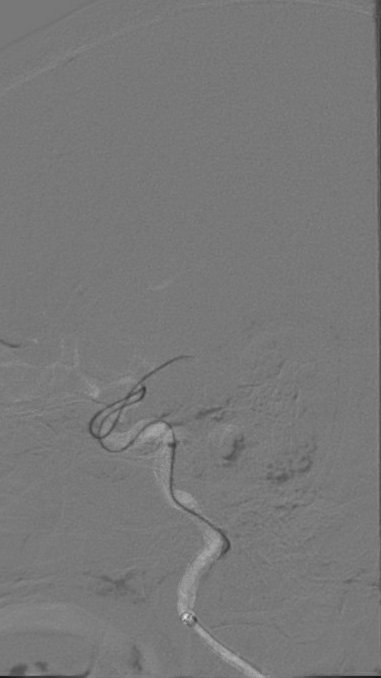

造影可见闭塞残端细小,结合多时相CT,考虑倾向于狭窄性病变。

过导丝。

释放支架后造影。